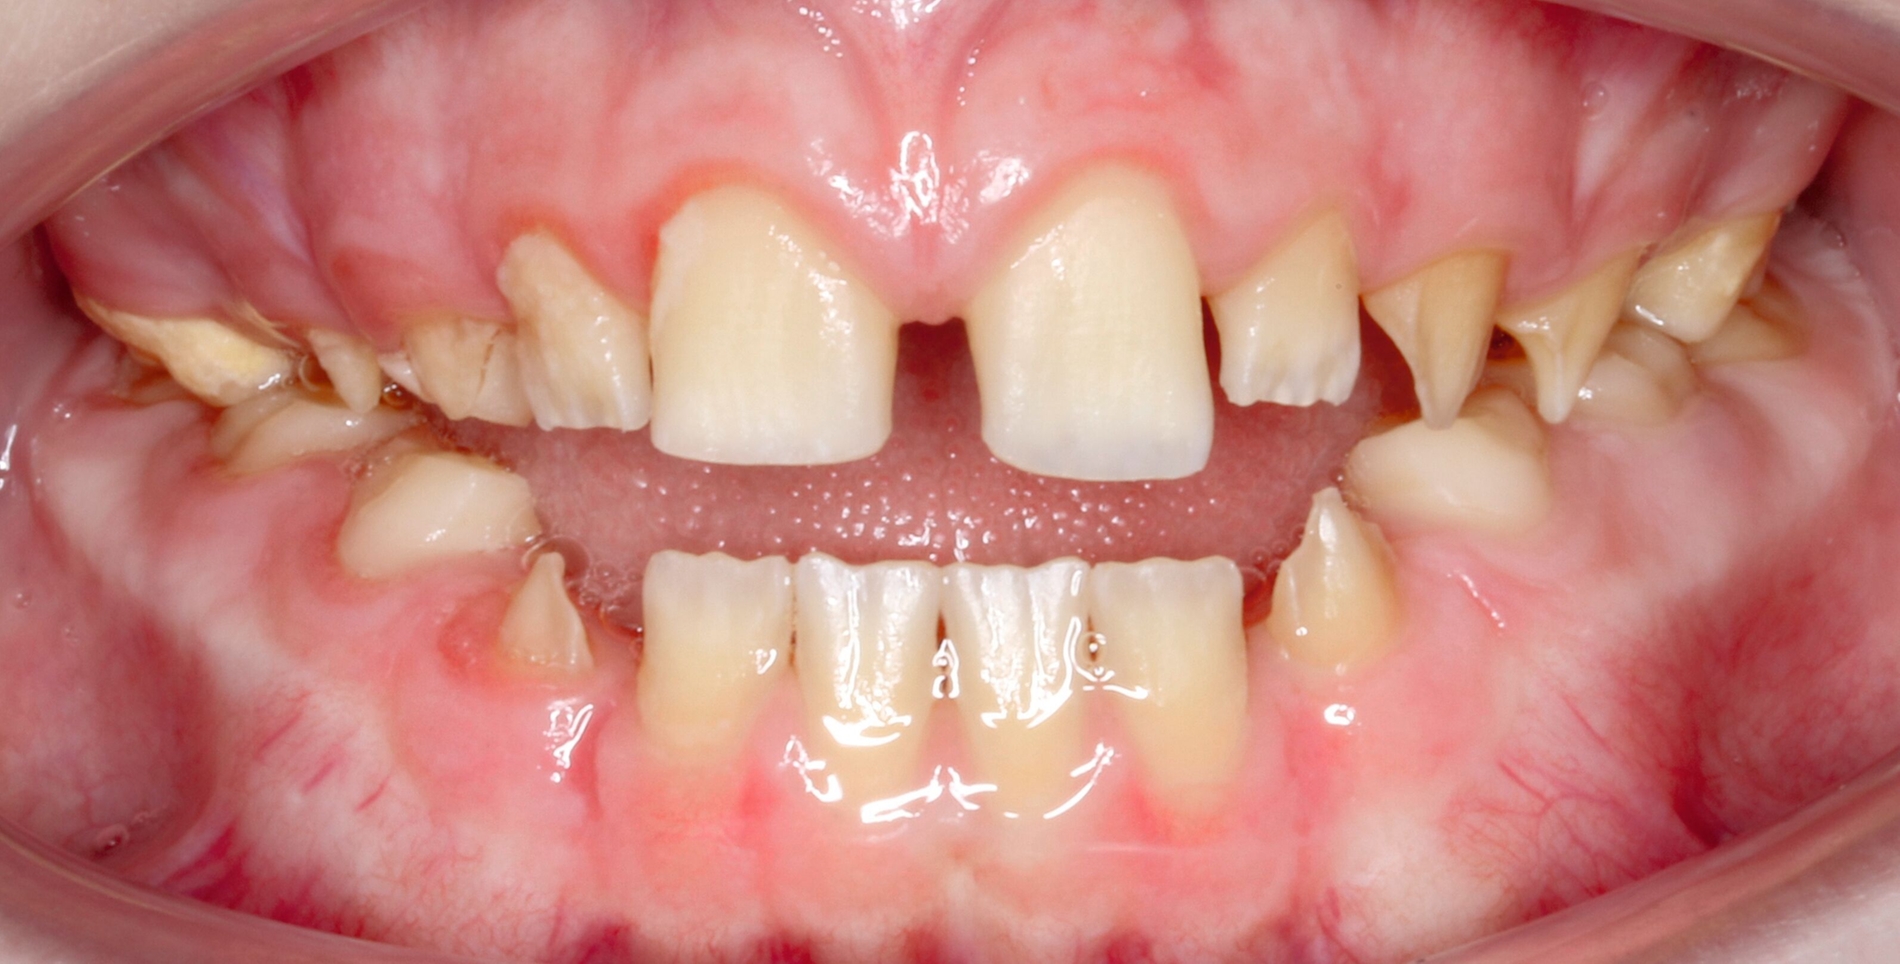

Klinisch zeigten sich ein nicht-kariöses Wechselgebiss mit generalisierter Schmelzhypoplasie an allen Zähnen sowie eine insuffiziente Mundhygiene. Zusätzlich bestanden eine fehlende Mittellinienübereinstimmung, ein Overbite von minus vier Millimetern und ein Overjet von sechs Millimetern (Abbildung 5), die sich phonetisch in einem interdentalen Sigmatismus äußerten. Röntgenologisch waren alle Zähne angelegt, jedoch war der Zahnschmelz stark reduziert oder vollständig fehlend (Abbildung 6).